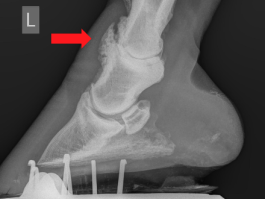

In manchen Fällen lassen sich an einem von Arthrose betroffenen Gelenk bereits von aussen und ohne Röntgenbild Knochenumbauprozesse wie z.B. ein „Spathöcker“ (vgl. Abb.4) oder eine „Schale“ (vgl. Abb.3) erkennen. Nach abgeschlossener Lahmheitsuntersuchung bzw. wenn bekannt ist, welches Gelenk betroffen ist, erfolgt in der Regel eine Röntgenuntersuchung.

Abb. 3: Äusserlich erkennbare knöcherne Auftreibung („Schale“) über dem Krongelenk links (roter Kreis) und Röntgenbild rechts. Der obere rote Pfeil im Röntgenbild zeigt auf das hochgradig veränderte Krongelenk ohne kaum mehr ersichtlichen Gelenkspalt und deutlichen knöchernen Brückenbildungen.